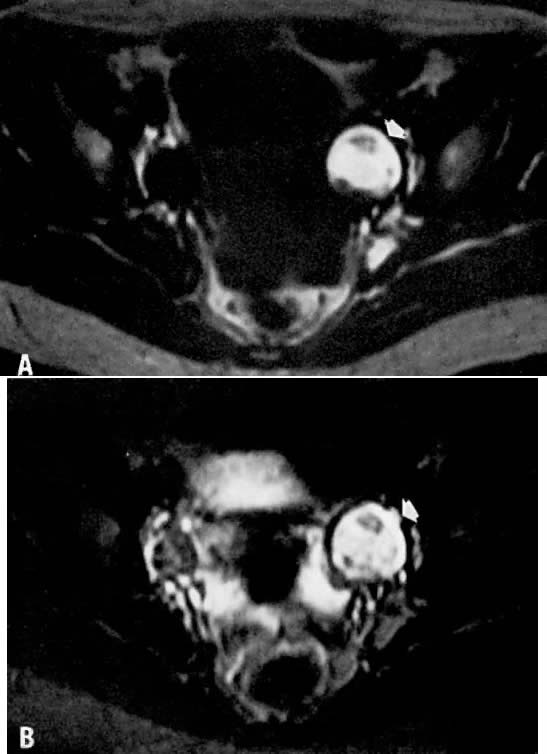

Fig. 8. A. Parametrial extension. Transverse T1-weighted image of a patient with cervical carcinoma extending into the parametrium ( white arrows ). The pelvic side walls ( open arrows) are uninvolved. B. T2-weighted image showing the cancer to have high signal intensity.